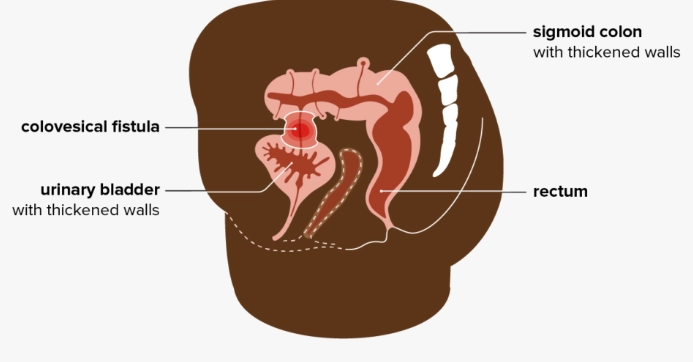

Rò đại tràng-bàng quang (Colovesical fistula)